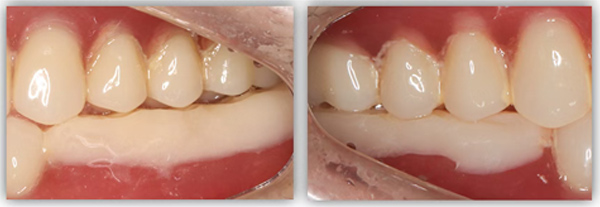

这位患者不到60岁,但由于后牙全部缺失多年,残留的前牙已松动且上下无法接触,他基本没办法正常咀嚼,人非常消瘦。完成治疗后我跟踪了这个病例一年,从前后对比照片可以看出,能正常吃东西后他的脸上渐渐也有肉了。